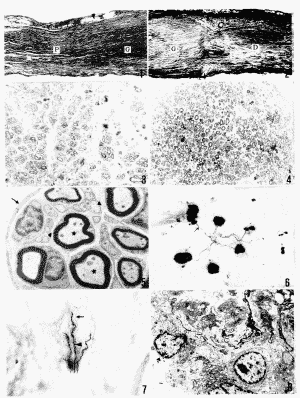

图1~7 为服用雷公藤甲素的异种神经移植实验组

图1,2 异种神经移植术后12周,近段坐骨神经(P)内的再生神经纤维通过近端吻合部(▲)长入移植神经段(G),继而越过远端吻合部(▲)向远段坐骨神经(D)生长 ×60

图3 异种神经移植术后4周,移植神经段内的再生神经纤维。甲苯胺蓝染色 ×240

图4 异种神经移植术后12周,移植神经内的再生神经纤维。甲苯胺蓝染色 ×240

图5 异种神经移植术后8周,移植神经段内再生的有髓纤维(★)和无髓纤维(▲)被神经束膜包绕(↑) ×5 000

图6 异种神经移植后12周,腓肠肌内的再生神经纤维(↑)与运动终板相连,AChE结合镀银染色 ×60

图7 异种神经移植术后24周,爪部真皮层内的再生神经末梢(▲)和行向表皮的游离神经末梢(↑) ×120

图8 未服用雷公藤甲素的异种神经移植对照组。术后4周移植神经段内的淋巴细胞(*)、巨噬细胞(▲)及细胞碎片 ×3 300